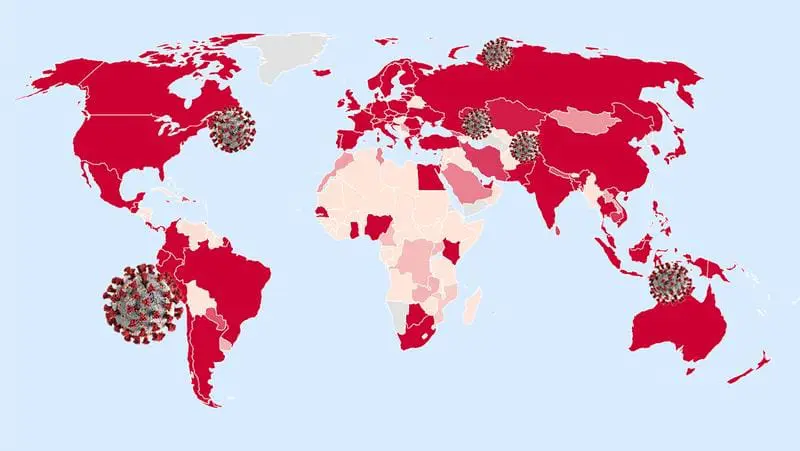

CoVerage: Früherkennung von SARS-CoV-2-Varianten mit hohem Risiko

Das Online-Tool CoVerage ermöglicht die Identifizierung und Charakterisierung besorgniserregender SARS-CoV-2-Varianten (Variants of Concern, VOC) bis zu drei Monate vor ihrer offiziellen Einstufung durch die Weltgesundheitsorganisation (WHO). Seit Beginn der Pandemie...